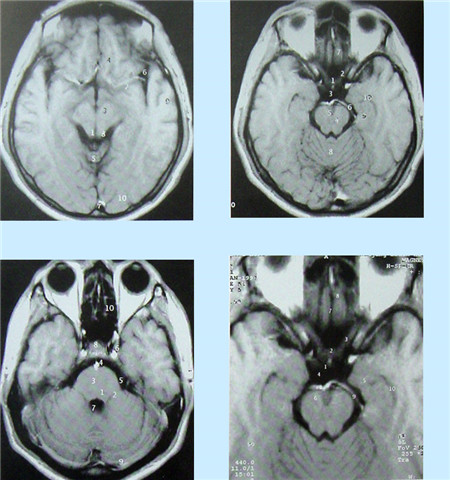

核磁共振血管成像(MRI)簡介

核磁共振(MRI)又叫核磁共振成像技術。是繼CT后醫學影像學的又一重大進步。自80年代應用以來,它以極快的速度得到發展。其基本原理是:將人體置于特殊的磁場中,用無線電射頻脈沖激發人體內氫原子核,引起氫原子核共振,并吸收能量。在停止射頻脈沖后,氫原子核按特定頻率發出射電信號,并將吸收的能量釋放出來,被體外的接受器收錄,經電子計算機處理獲得圖像,這就叫做核磁共振成像。

核磁共振成像無電離,對機體沒有不良影響。MRI對檢測腦內血腫、腦外血腫、腦腫瘤、顱內動脈瘤、動靜脈血管畸形、腦缺血、椎管內腫瘤、脊髓空洞癥和脊髓積水等顱腦常見疾病很有效。

核磁共振成像設備價格昂貴,檢查費用也較高,它與CT都可以提供斷層的靜態掃描圖像。

數字減影血管造影DSA腦血管圖像顯示                                                      核磁共振MRI掃描腦組織圖像